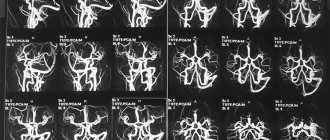

Подробно об энцефалограмме Суть обследования заключается в фиксации электрической активности нейронов структурных образований головного